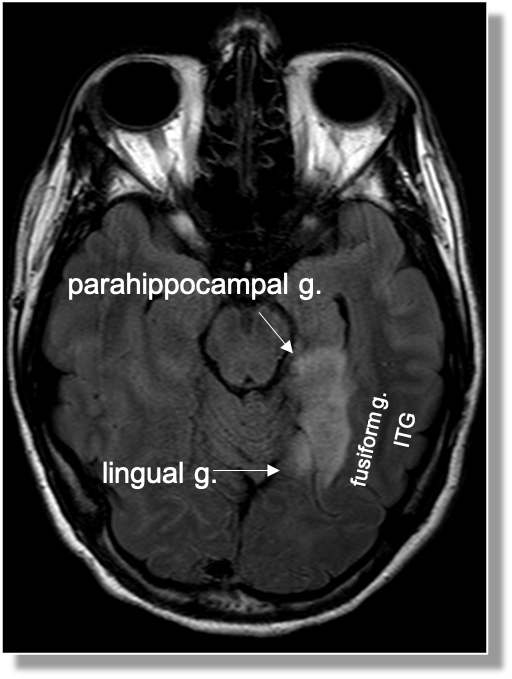

Gyral anatomy of inf occipitotemporal surface: The inf. temp. gyrus wraps from lateral https://abs.twimg.com/emoji/v2/... draggable="false" alt="➡️" title="Pfeil nach rechts" aria-label="Emoji: Pfeil nach rechts">inferior. The fusiform and lingual gyri span from occipital lobe posteriorly to temporal lobe anteriorly. Parahippocampal is medial temporal (anterior continuation of the lingual g).

https://abs.twimg.com/emoji/v2/... draggable="false" alt="➡️" title="Pfeil nach rechts" aria-label="Emoji: Pfeil nach rechts">inferior. The fusiform and lingual gyri span from occipital lobe posteriorly to temporal lobe anteriorly. Parahippocampal is medial temporal (anterior continuation of the lingual g).

The lingual gyrus is involved in holistic visual and word processing, encoding visual memories, imagery, and dreaming. The ganglioglioma in the shown case is centered in the lingual gyrus.

Fusiform g is just lateral to lingual g on the inf surface of temporal lobe, separated by collateral sulcus. It& #39;s medial to the ITG, separated by ITS. Involved in face and body recognition; word form recognition (on left). (Fusiform g was not definitively involved by tumor). 9/13

Parahippocampal g. is anterior continuation of lingual g. Part of Limbic System. Important in memory encoding and retrieval, visual and social contextualizing.

inferior. The fusiform and lingual gyri span from occipital lobe posteriorly to temporal lobe anteriorly. Parahippocampal is medial temporal (anterior continuation of the lingual g).6/13" title="Gyral anatomy of inf occipitotemporal surface: The inf. temp. gyrus wraps from lateralhttps://abs.twimg.com/emoji/v2/... draggable="false" alt="➡️" title="Pfeil nach rechts" aria-label="Emoji: Pfeil nach rechts">inferior. The fusiform and lingual gyri span from occipital lobe posteriorly to temporal lobe anteriorly. Parahippocampal is medial temporal (anterior continuation of the lingual g).6/13" class="img-responsive" style="max-width:100%;"/>

inferior. The fusiform and lingual gyri span from occipital lobe posteriorly to temporal lobe anteriorly. Parahippocampal is medial temporal (anterior continuation of the lingual g).6/13" title="Gyral anatomy of inf occipitotemporal surface: The inf. temp. gyrus wraps from lateralhttps://abs.twimg.com/emoji/v2/... draggable="false" alt="➡️" title="Pfeil nach rechts" aria-label="Emoji: Pfeil nach rechts">inferior. The fusiform and lingual gyri span from occipital lobe posteriorly to temporal lobe anteriorly. Parahippocampal is medial temporal (anterior continuation of the lingual g).6/13" class="img-responsive" style="max-width:100%;"/>